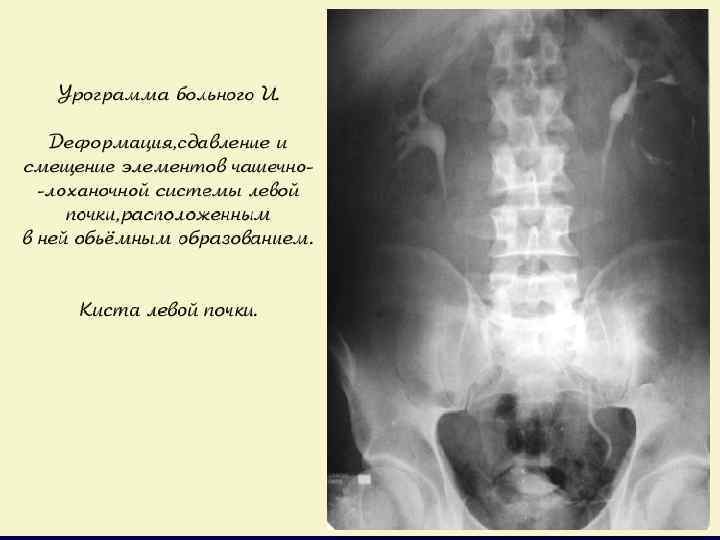

ПРИЗНАКИ ОПУХОЛИ ПРИ В/ВЕННОЙ УРОГРАФИИ

в/венная урография – кальцинированное объемное образование в н/полюсе левой почки: киста? , опухоль? , эхинококк?